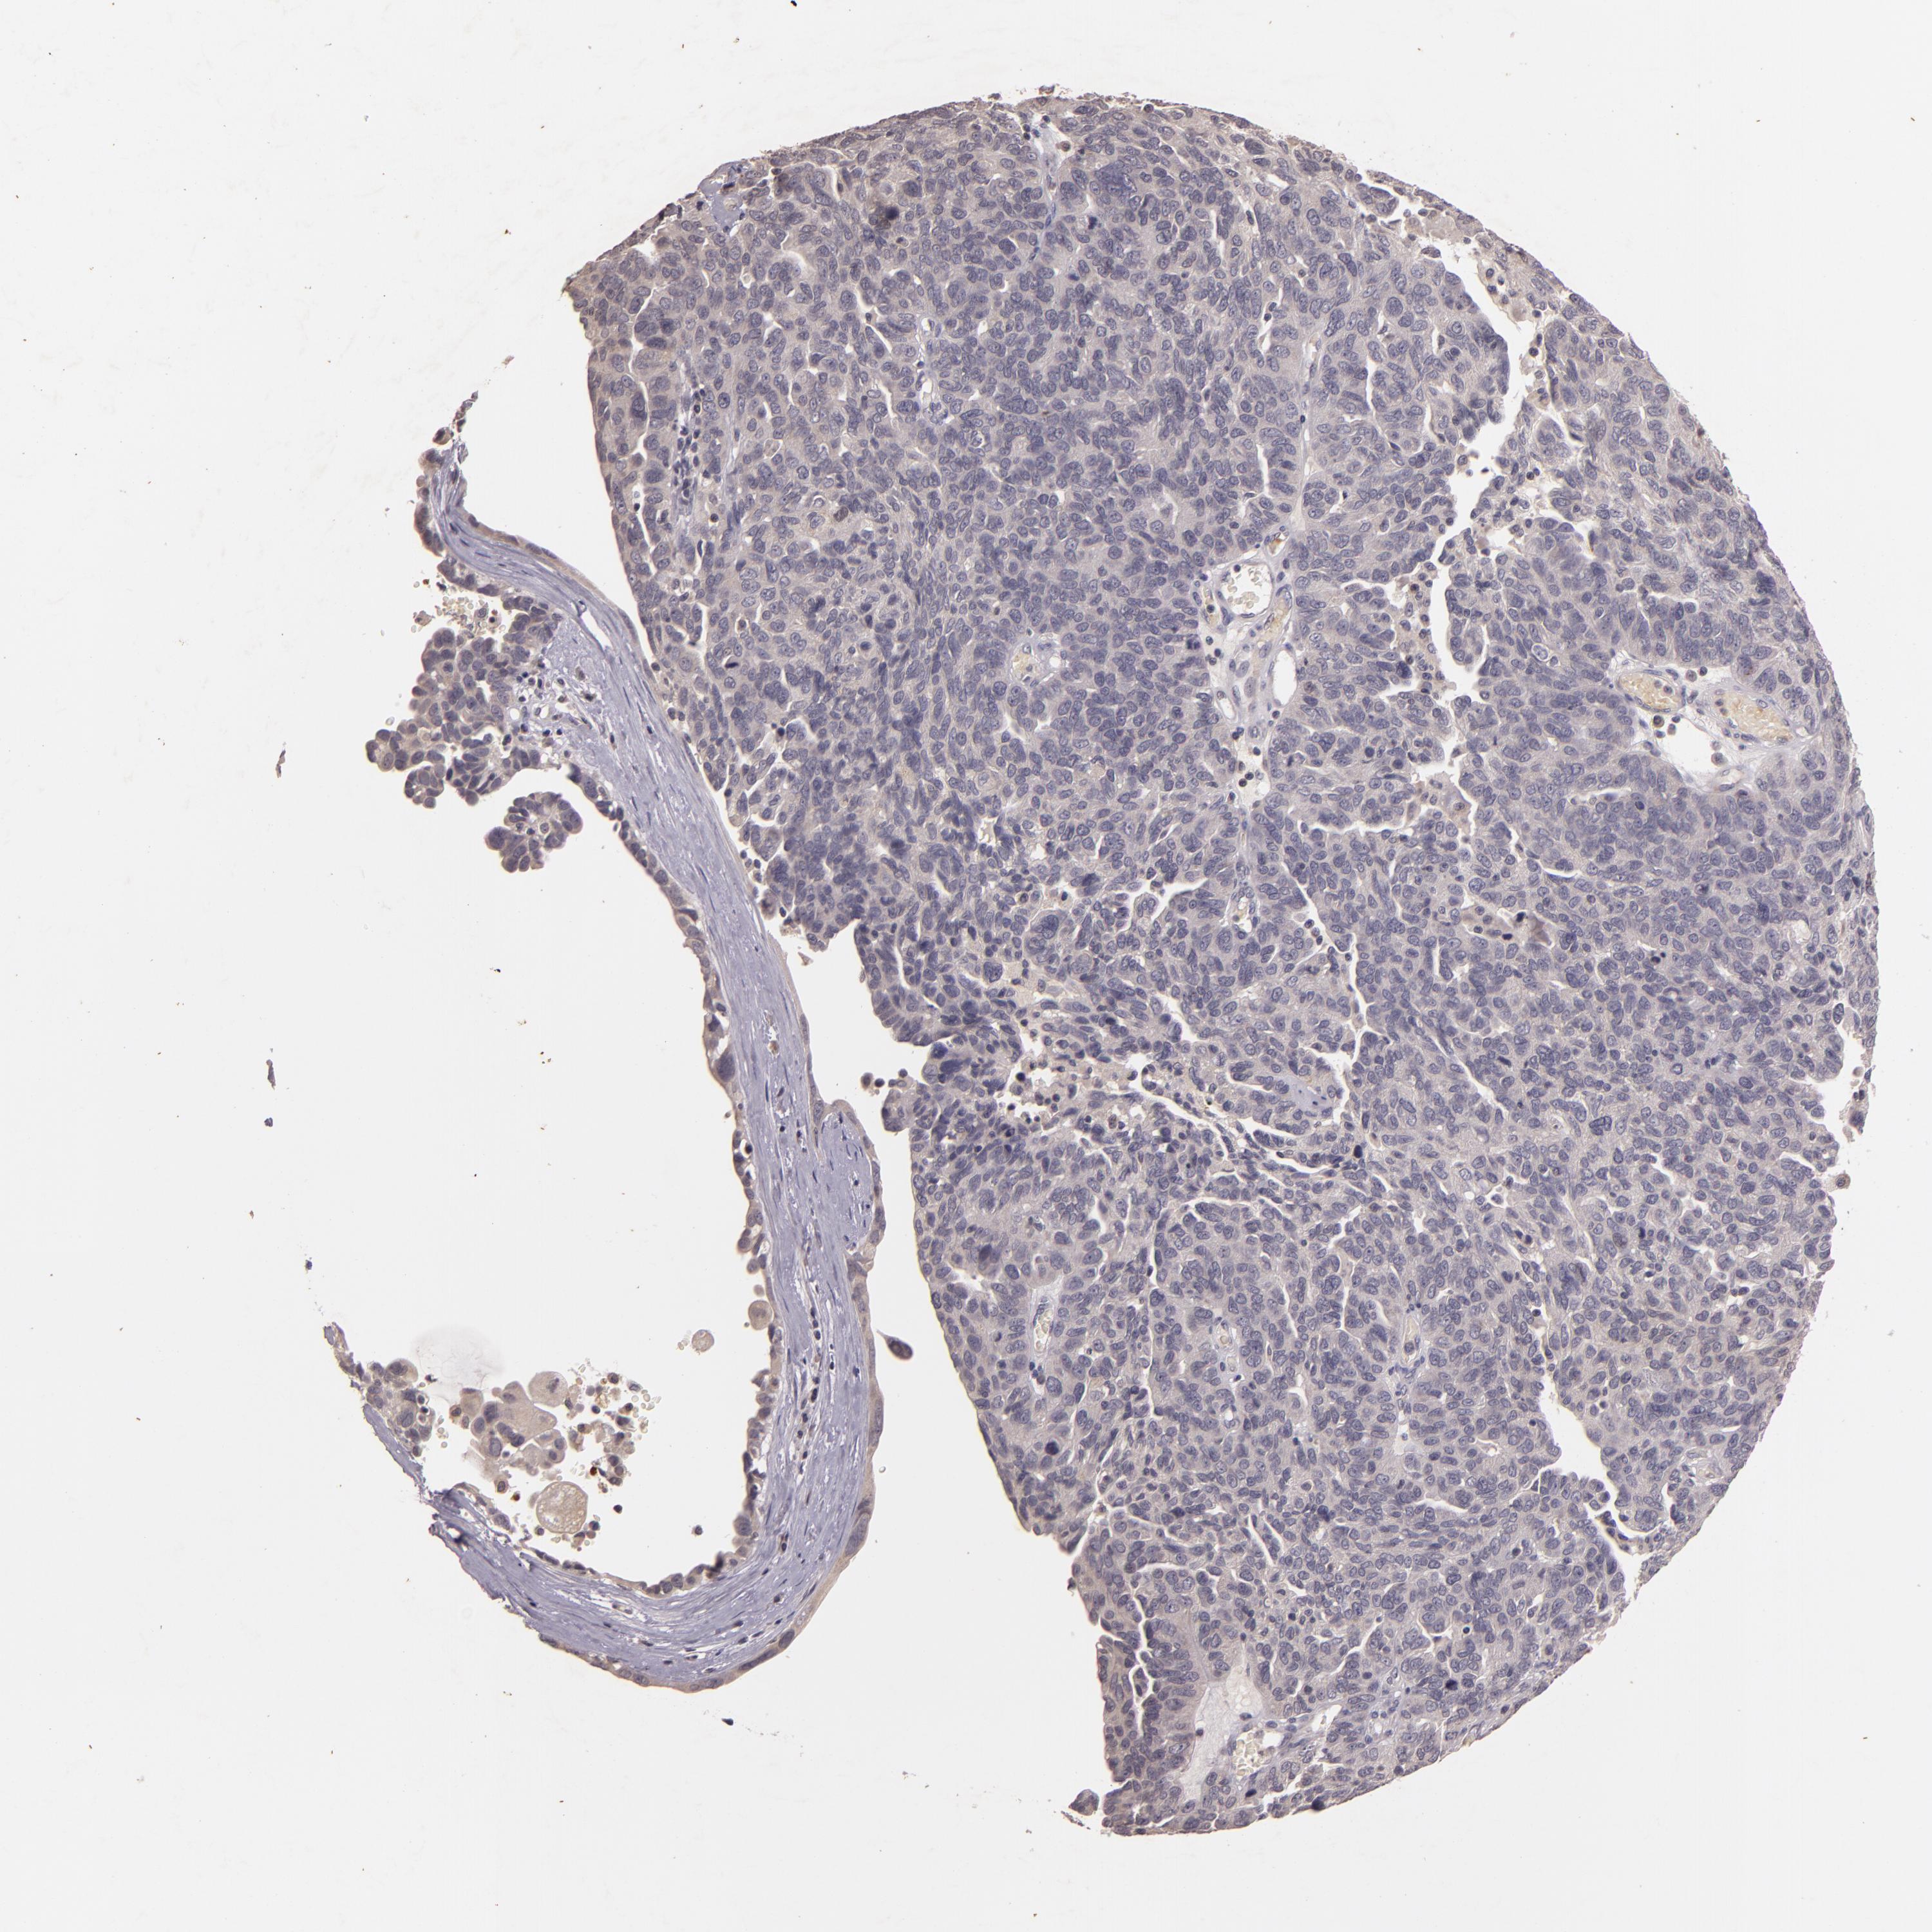

OVARIAN CANCER - Protein expressioni

A mouse-over function shows sample information and annotation data. Click on an image to view it in a full screen mode. Samples can be filtered based on level of antibody staining by selecting one or several of the following categories: high, medium, low and not detected. The assay and annotation is described here.

Note that samples used for immunohistochemistry by the Human Protein Atlas do not correspond to samples in the TCGA dataset.

Antibody stainingi

Antibody staining in the annotated cell types in the current human tissue is reported as not detected, low, medium, or high, based on conventional immunohistochemistry profiling in selected tissues. This score is based on the combination of the staining intensity and fraction of stained cells.

Each image is clickable and will lead to virtual microscopy that enables deeper exploration of all samples and also displays staining intensity scores, fraction scores and subcellular localization as well as patient and tissue information for each sample.

Antibody HPA003425

Antibody CAB002170

Cystadenocarcinoma, serous, NOS

Cystadenocarcinoma, mucinous, NOS

Carcinoma, endometroid